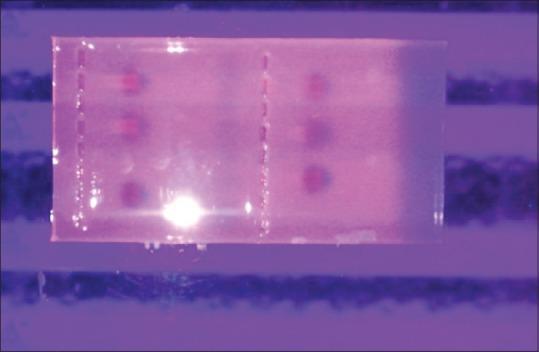

To study mutated/wild type p53 expression using immunohistochemistry and detect HPV-16 presence using polymerase chain reaction (PCR), in OSCC and correlating their expression.

Immunohistochemical staining for p53 molecule in 24 sections of OSCC followed by DNA extraction of the cases using qiagen extraction kit and subsequent HPV-16 detection using PCR technique.

Out of 24 cases of OSCC, twenty cases were positive for P 53 expression and four cases were negative for P 53 expression. Out of the four negative cases, one case was detected positive for HPV-16.